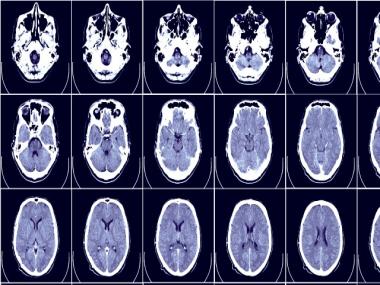

Representatiomal image. Wikimedia Commons

National Epilepsy Day is marked on 17 November annually to create awareness about the medical issue. The day is also used for making people aware of the symptoms and treatment of the disease. Epilepsy is a non-communicable disease in which recurrent seizures occur due to the brain generating sudden, abnormal bursts of electrical energy.